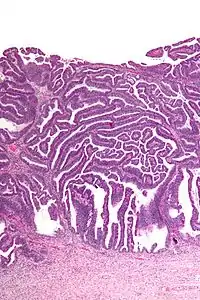

| Micrograph of a villoglandular adenocarcinoma the cervix. H&E stain. | |

The name of the lesion describes it microscopic appearance. It has nipple-like structures with fibrovascular cores (papillae) that are long in relation to their width (villus-like), which are covered with a glandular pseudostratified columnar epithelium.

Intermediate magnification